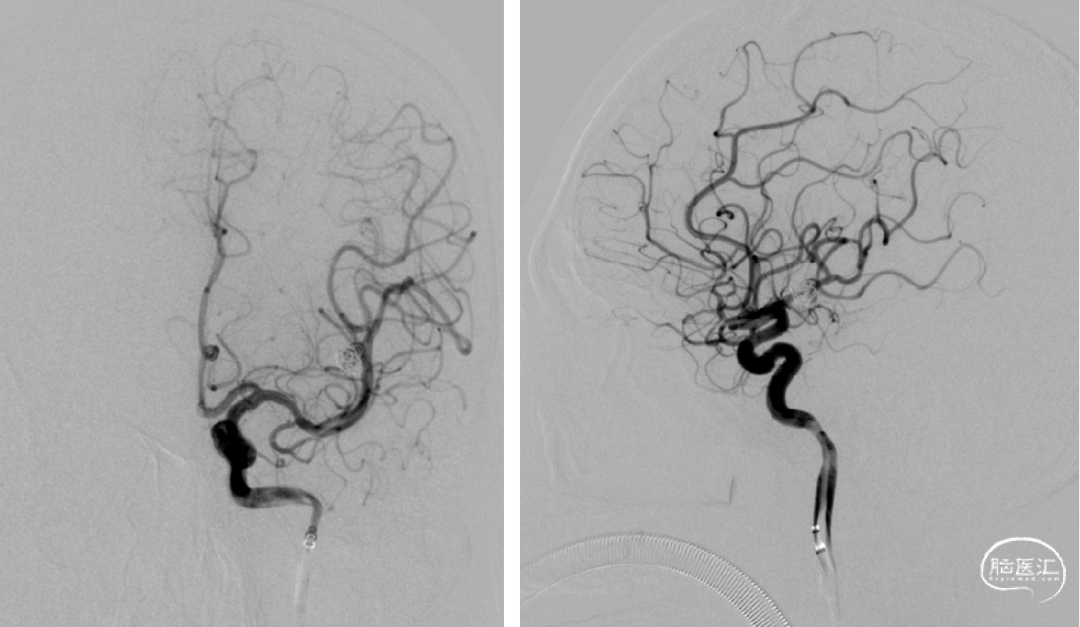

术后磁共振无脑梗及低灌注

术后半年复查,动脉瘤消失,载瘤动脉通畅